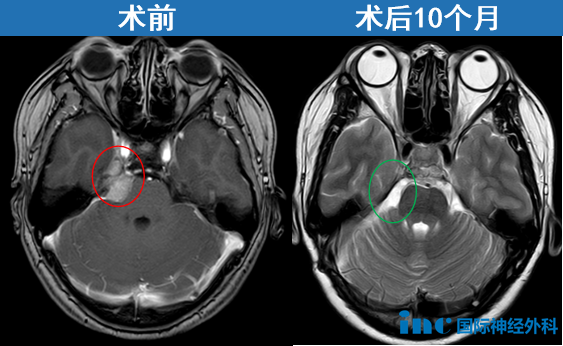

福教授指出,从两次核磁共振的对比来看,肿瘤情况基本稳定,未见明显生长。因此他建议暂不采取任何积极干预,而是6个月后再次复查核磁,密切观察肿瘤是否有增大或扩散的趋势。

在北京天坛医院,INC福教授为她成功手术——“我在ICU里面呆了4个多小时就出来了,第2天下床,第9天出院。”点击阅读:天坛医院手术纪实|4.5cm脑膜瘤紧压脑干成功手术,勇敢辣妈的彪悍人生!

41岁的周女士同样在体检中发现桥小脑角(CPA)区脑膜瘤。肿瘤虽小,位置却极其棘手:与纤细的滑车神经、三叉神经紧紧粘连,同时还压迫桥脑和中脑——这是生命的中枢。她没有等到剧烈头痛或面瘫偏瘫出现,正是这份体检报告,让她在神经功能尚完好时抓住了治疗的“黄金窗口期”,最终由巴教授主刀完成高难度手术,及早解除风险。